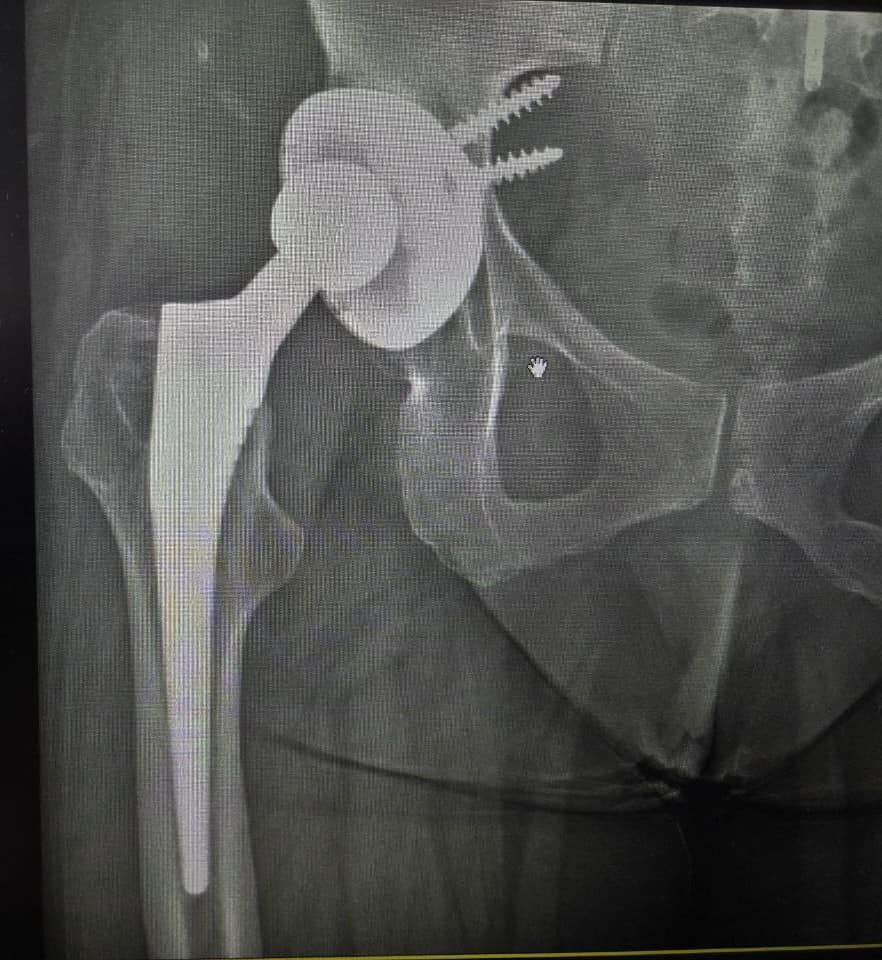

Вывих тазобедренного сустава спустя 12 лет после эндопротезирования

Удачно выполненное эндопротезирование тазобедренного сустава способно решить проблему боли и нестабильности сочленения с минимальным риском осложнений.Однако со временем риск возникновения вторичных травм (прежде всего – вывихов) увеличивается.На фото мы видим пример, когда вывих тазобедренного сустава произошёл спустя 12 лет после инсталляции эндопротеза.

Ввиду вероятности повторных вывихов, высокой интеграции части сочленения с эндопротезом, а также с целью дополнительной стабильности имплантата, было принято решение установить эндопротез тазобедренного сустава с двойной мобильностью.Такой имплантат способен минимизировать риски расшатывания вертлужной губы и обеспечит выживание сустава в 80% случаев даже через 20 лет.